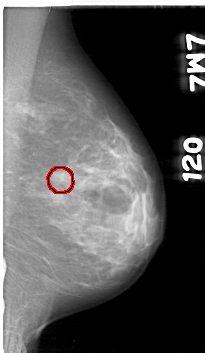

D_4057_1.RIGHT_CC

RIGHT_CC LINES 5071 PIXELS_PER_LINE 2716 BITS_PER_PIXEL 12 RESOLUTION 43.5 NON_OVERLAY

FILE: D_4057_1.LEFT_CC.OVERLAY

TOTAL_ABNORMALITIES 1

ABNORMALITY 1

LESION_TYPE MASS SHAPE IRREGULAR MARGINS OBSCURED

ASSESSMENT 0

SUBTLETY 3

PATHOLOGY BENIGN

TOTAL_OUTLINES 1

BOUNDARY